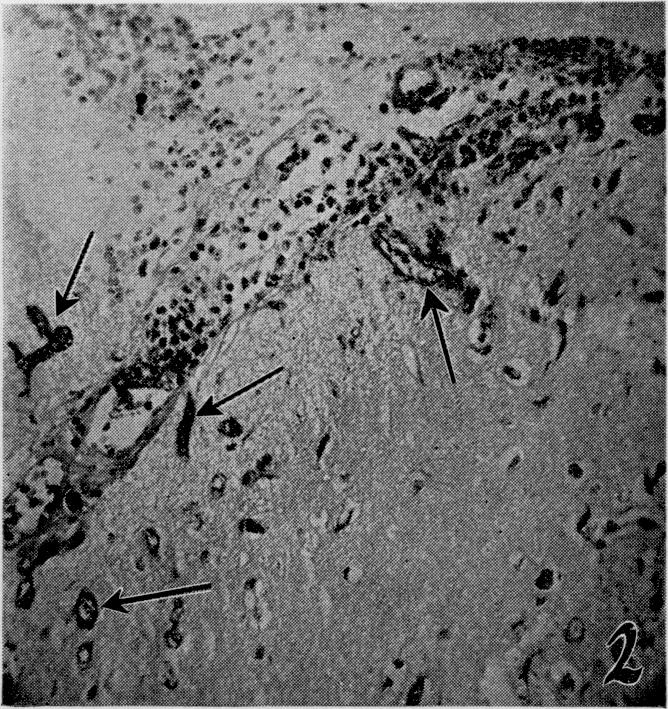

The effects of metabolic alterations on experimental Rhizopus oryzae (mucormycosis) infection.

Yale J Biol Med. 1956 Sep;29(1):23-32.